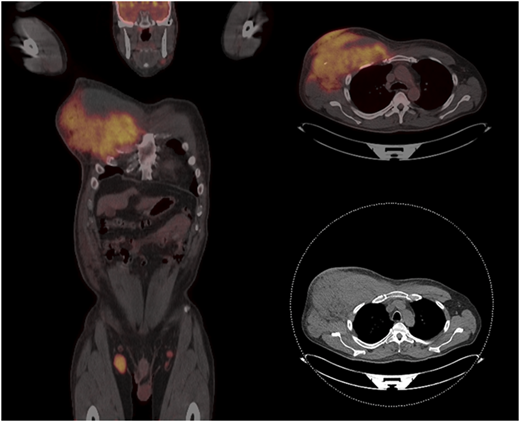

Patient 2 was a 61-year-old man who had presented with a right neck mass 8 years ago. A biopsy showed FL grade 1. He had undergone active observation until several months ago, when he noted right axillary swelling. He was evaluated in the clinic and was found to have an extensive mass in his right axilla and infiltrating the chest wall (Figure 2). A biopsy showed transformation to an aggressive lymphoma with a Ki67 of 95% and sheets of mitotically active intermediate to large cells with a high nucleus/cytoplasm ratio, CD20+CD10+MYC+BCL2+. Subsequent fluorescence in situ hybridization confirmed rearrangements of MYC and BCL2.

Patient with FL transforming to HGBL-DHL/THL, showing massive infiltration of the right chest wall and axillary adenopathy.